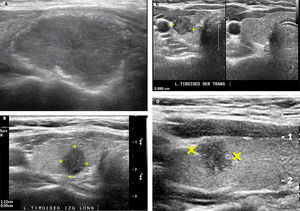

SIGNOS ECOGRÁFICOS DE MALIGNIDAD DE LOS NÓDULOS TIROIDEOSLas características ecográficas de los nódulos que sugieren malignidad son: nódulo sólido hipoecogénico o marcadamente hipoecogénico, más alto que ancho, de bordes irregulares, microlobulados o espiculados y con microcalcificaciones (Figura 7a, 7b, 7c y 7d). La heterogeneidad no es un signo específico, lo mismo para la naturaleza sólida. Los contornos mal definidos tampoco. La hipoecogenicidad en nódulos menores de 10mm tiene menor valor predictivo positivo que en nódulos de más de 10 mm3. Las calcificaciones a modo de cápsula tienen alta especificidad cuando se encuentran asociadas a un nódulo que claramente las rebasa (Figura 8). Considerando sólo el tamaño de los nódulos, se sugiere puncionar los nódulos sólidos mayores de 10mm de diámetro y los sólido-quísticos mayores de 20mm. Mientras más criterios de malignidad presenta el nódulo, mayor será la probabilidad de malignidad3,4,8,9,12.

Nódulos tiroideos con caracteres ecográficos de malignidad.

A: Nódulo tiroideo sólido, marcadamente hipoecogénico, además presenta microcalcificaciones en la periferia (Ca papilar).

B: Nódulo tiroideo sólido más alto que ancho: diámetro anteroposterior (alto) mayor que el diámetro longitudinal (ancho). (Ca papilar).

C: Nódulo tiroideo sólido, en un corte transversal, adyacente a la arteria carótida común, de contornos microlobulados, hipoecogénico y heterogéneo. (Ca papilar).

D: Nódulo tiroideo sólido, con microcalcificaciones en el interior y periferia. (Ca papilar).